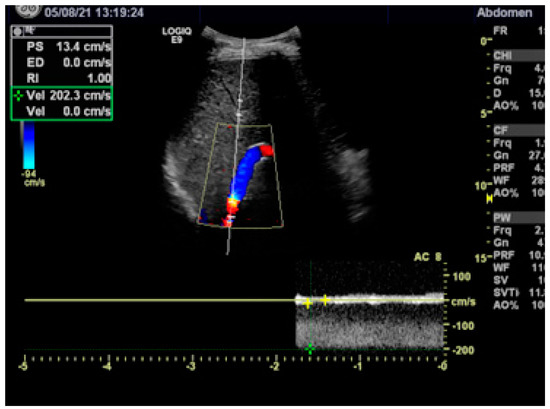

2.2. TIPS

2.2.2. Technique of TIPS Implantation

3.1. Hemodynamics